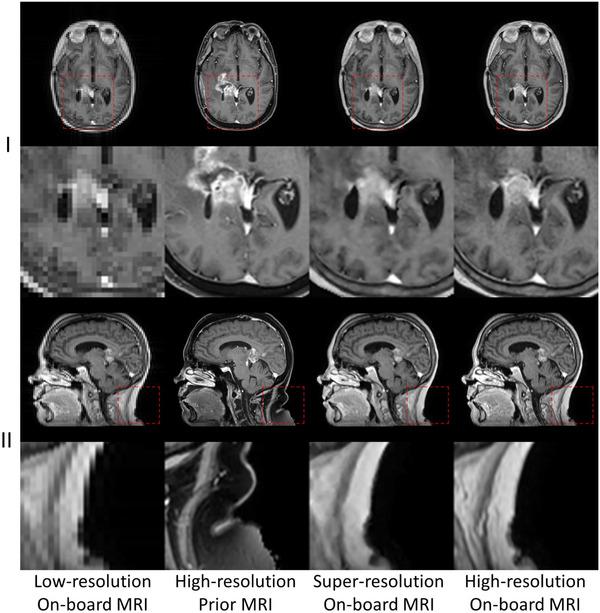

To achieve super-resolution for on-board MRI, this study proposed a universal anatomical mapping and patient-specific prior implicit neural representation (USINR) framework. Unlike traditional methods that interpolate solely based on individual on-board MR images, USINR can fully utilize the patient-specific anatomical information from a high-resolution prior MRI. In addition, USINR leverages knowledge about universal mapping between population-based prior MRIs and on-board MRIs, elevating the upper bound of super-resolution performance and enabling faster on-board fine-tuning.

USINR was evaluated on three datasets, including IXI, BraTS, and an in-house abdominal dataset. It achieved state-of-the-art performance on all of them. For example, on the BraTS dataset, USINR was trained on 1151 paired training samples (for universal anatomical mapping) and tested on 50 patients. It achieved average SSIM, PSNR, and LPIPS scores of 0.9656, 37.12, and 0.0214, respectively, significantly outperforming the published state-of-the-art method SuperFormer, whose corresponding scores were 0.9488, 35.83, and 0.0388. Furthermore, USINR can complete patient-specific training in less than one minute, rendering it a favorable solution in time-constrained ART workflows. In addition to large-scale dataset evaluations, a case study was conducted on an in-house patient at UT Southwestern Medical Center. This case study included two MRI scans (a prior scan for plan simulation and a new one for on-board imaging) from a single patient with a long interval between two scans, during which the tumor size underwent a significant change. Despite these substantial anatomical changes between prior and on-board imaging, USINR was able to accurately capture the change in tumor size, highlighting its robustness for clinical applications.

为实现机载MRI的超分辨率,本研究提出了一种通用解剖映射和患者特异性先验隐式神经表示(USINR)框架。与传统方法仅基于单个机载MR图像进行插值不同,USINR可以充分利用来自高分辨率先验MRI的患者特异性解剖信息。此外,USINR利用了基于人群的先验MRI与机载MRI之间通用映射的知识,提高了超分辨率性能的上限,并实现了更快的机载微调。

USINR在三个数据集上进行了评估,包括IXI、BraTS和一个内部腹部数据集。在所有这些数据集上,它都取得了领先的性能。例如,在BraTS数据集上,USINR在1151对训练样本(用于通用解剖映射)上进行训练,并在50名患者上进行测试。它分别实现了平均结构相似性指数(SSIM)、峰值信噪比(PSNR)和学习感知图像补丁相似度(LPIPS)分数为0.9656、37.12和0.0214,显著优于已发表的领先方法SuperFormer,其相应分数分别为0.9488、35.83和0.0388。此外,USINR可以在不到一分钟的时间内完成患者特异性训练,使其成为时间受限的ART工作流程中的理想解决方案。除了大规模数据集评估外,还在德克萨斯大学西南医学中心的一名内部患者身上进行了案例研究。该案例研究包括来自一名患者的两次MRI扫描(一次用于计划模拟的先验扫描和一次用于机载成像的新扫描),两次扫描之间间隔较长,在此期间肿瘤大小发生了显著变化。尽管先验成像和机载成像之间存在这些显著的解剖结构变化,USINR仍能够准确捕捉肿瘤大小的变化,突出了其在临床应用中的稳健性。